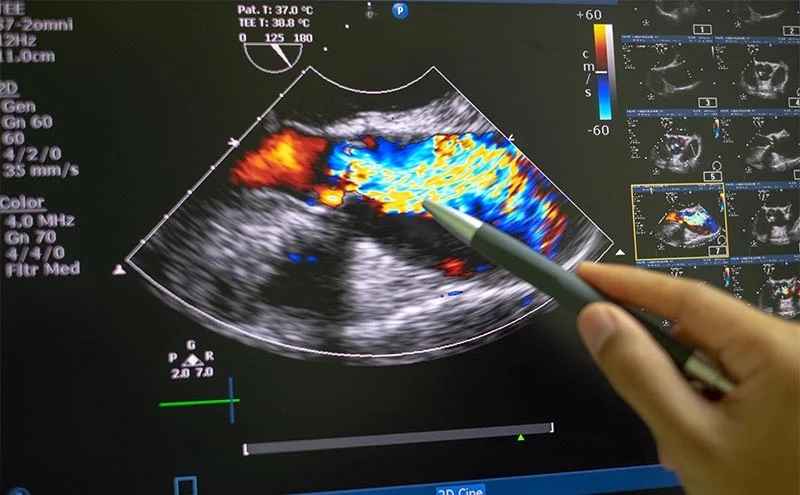

اکوی مری قلب که با نام علمی اکوکاردیوگرافی از راه مری (Transesophageal Echocardiography یا TEE) شناخته میشود، یک ابزار تشخیصی بسیار قدرتمند و دقیق در علم کاردیولوژی است. در مواردی که پزشک نیاز به مشاهده جزئیات بسیار ظریف قلب دارد، اکوی مری قلب به دلیل ارائه تصاویری با وضوح بالا، برای بیمار تجویز می شود. این روش تخصصی، به دلیل نزدیکی مری به حفرههای پشتی قلب، میتواند تصاویری به مراتب واضحتر از اکوی معمولی قلب ارائه دهد.

اکوی مری قلب یک نوع ویژه از اکوکاردیوگرافی است که در آن، یک پروب کوچک از طریق مری (لولهای که غذا را به معده میرساند) وارد بدن میشود. از آنجا که مری مستقیماً پشت قلب قرار دارد، پروب میتواند بدون تداخل ریهها، قفسه سینه یا چربی زیر پوست، تصاویر بسیار نزدیکی از ساختار قلب بگیرد. این وضوح بالا، امکان تشخیص لخته خون با اکوی مری و سایر جزئیات ریز را فراهم میآورد. نکته ی مهم اینجاست که شما باید این تست را در مرکز اکوی قلب تخصصی در شمال تهران انجام بدهید تا از صحت تست انجام شده مطمئن باشید.

| کیفیت تصویر | مناسب برای ارزیابی کلی و ساختارهای جلویی قلب | بسیار واضح؛ برای ساختارهای پشتی و دریچهها |

- بررسی دریچههای قلب: برای ارزیابی دقیق عفونتها (اندوکاردیت) یا نارساییهای کوچک دریچهای که با اکوی معمولی قابل تشخیص نیستند.